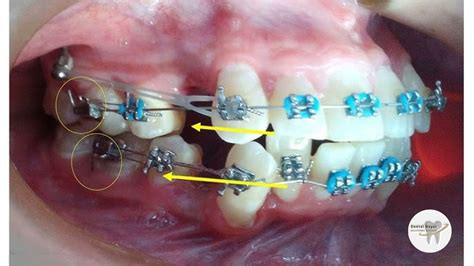

Evolución a 3 meses de Tratamiento de Ortodoncia